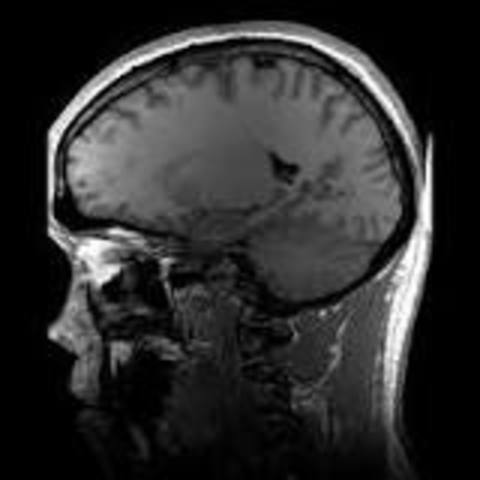

• MRI

MRI

Le MRI est cree en 1971. Cette invention a changer notre monde qu'on nous vivons dans maintenant parce que le MRI est une invention qui a sauver la vie de plusieur personne est qui vas sauver la vie de plusieur personne dans le futur.